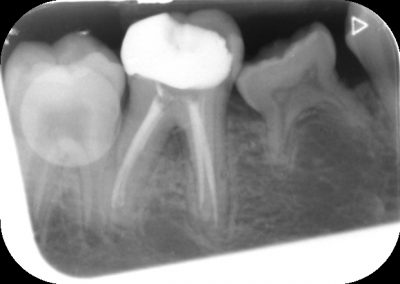

During the consultation, the dentist will first listen to your concerns and carry out appropriate tests to identify the right tooth that is causing pain. As a part of the diagnosis, your dentist will carry out various clinical tests to identify the right tooth and will take some radiographs which can aid in the diagnosis.

An access cavity is placed on the surface where the patient bites, to reach the root canals of the tooth. Once all the canals are identified, small files are used to remove the infected pulp.

Files of different sizes are used to eliminate bacteria and infection and to shape the canals. The canals are disinfected thoroughly with irrigants and later the canals will be sealed in 3 dimensions with a special medicament called gutta-percha to prevent reinfection of the tooth and the access cavity will be sealed with a temporary filling.